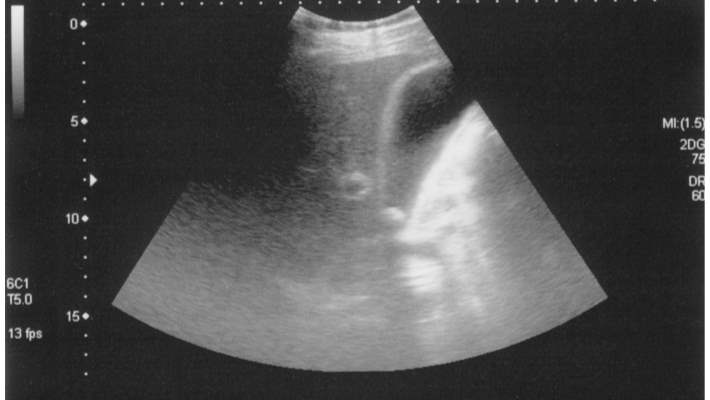

Anneme cekilen tomografide karaciger buyuklugu normaldir. Karaciger parankim dansitesu normalden dusuktur.(hepatosteatoz). Intrahepatik safra yollari ve vaskuler yapilar tabidir. Safra kesesinin volumu, duvar kalinligi normaldir. Safra kesesi boynunda 4 mm ve fundusta 8 mm boyutunda hiperdens kalkuller izlenmistir.safra kesesi bilobule gorunumdedir. Koledok capi normal genisliktedir.dalak buyuklugu normal olup, parankim danaitesi homojendir.pankreas ve paraaortik alanlar tabii izlenmektedir.her iki bobrek parankim dansitesi,toplayici sistemleri tabidir.bilateral surrenal glamdlar tabiidir. Mesane homojen izlenmektedir.batin ici sivi serbest sivi izlenmemiatir. Sol overde 4.5 cm boyutunda hipodena kist izlensi. Umblikal herni izlendi. ( hocam durum nedir )